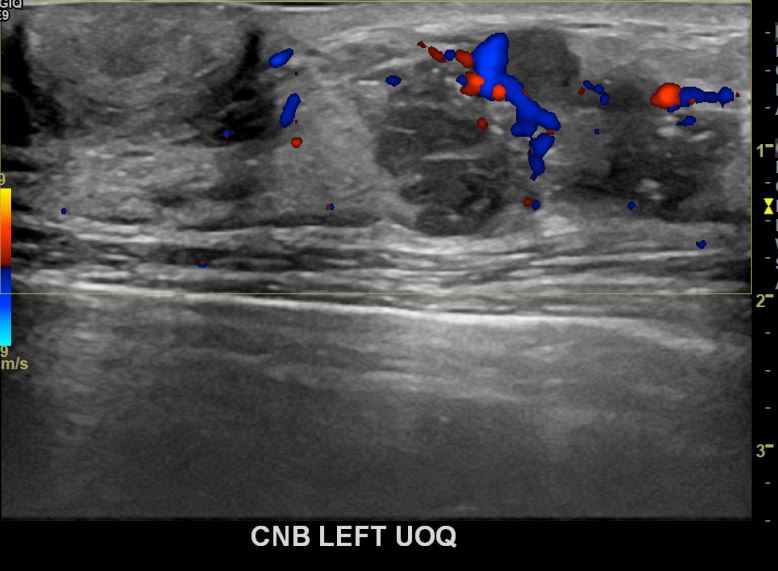

아산유외과개원후 675번째 유방암진단

상기환자 외부검사상 이상소견으로 내원하신 50대여성으로 좌측에 의심스러운혹 조직검사시행해 유방암 진단되었습니다.